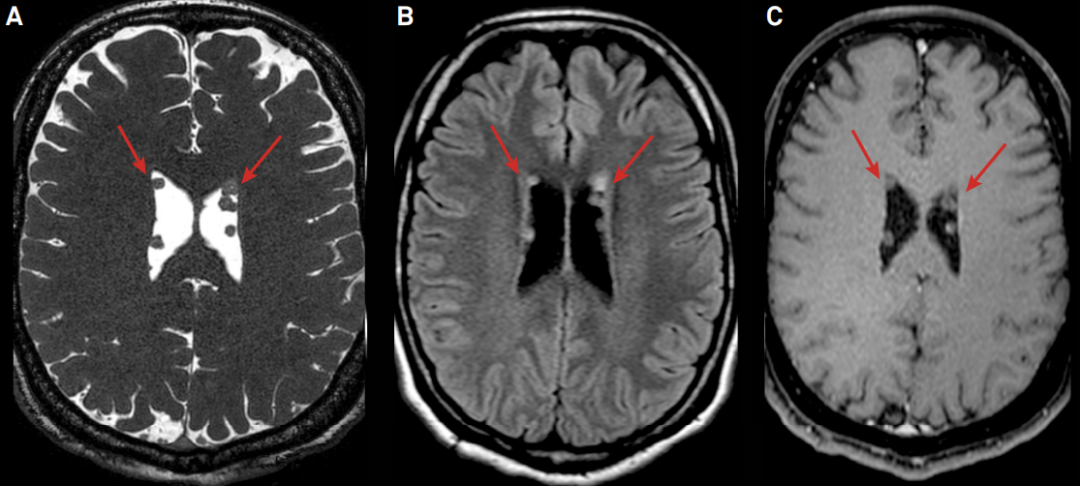

男,49 岁,当地医院体检发现侧脑室壁结节,考虑占位,随来我院进一步检查,MR 如下图绿箭头所示。

右侧侧脑室壁见结节样异常信号,T2WI 周围低信号,中心高信号,T1WI 呈周围等信号,中心低信号,FLAIR 呈高信号,DWI 及 ADC 图呈等信号。

高年资医生阅片之后告诉患者不要有任何担心,该吃吃该喝喝,并不是占位。